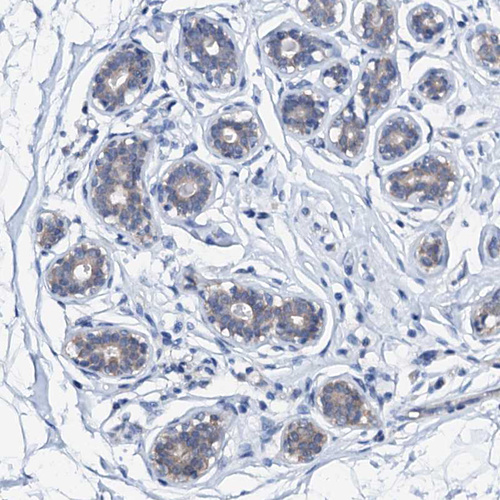

Immunohistochemical staining of human lactating breast shows strong cytoplasmic positivity in glandular cells.